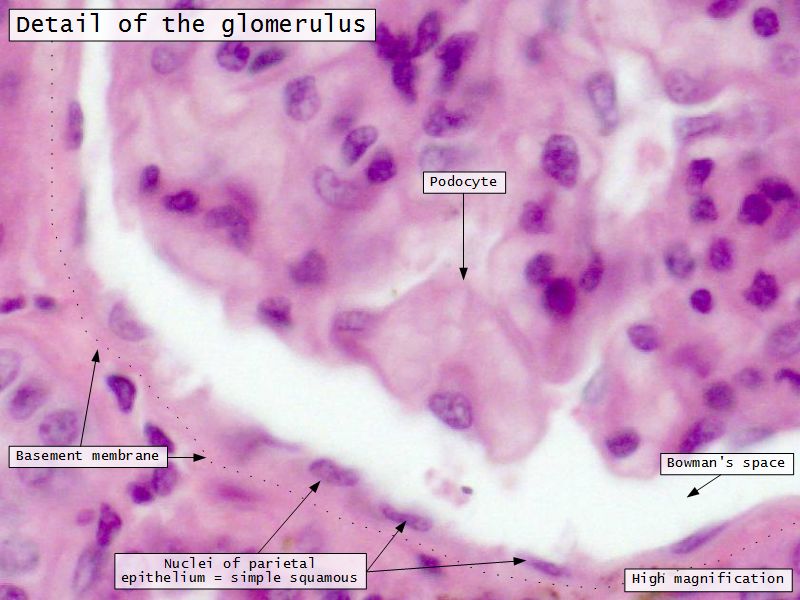

Epithelium layers

- Capillary endothelium

- Visceral layer of epithelium

- Podocytes

- Resting on glomerular basement membrane

- Capsular space

- Parietal layer of epithelium

- Simple squamous epithelium

Glomerular filtration barrier

- Three layers

- Fenestrated epithelium

- Exclude blood cells & platelets

- Glomerular basement membrane

- Main filtration barrier

- Thick

- Fused epithelial & endothelial BM

- Replenished by podocytes due to removal by mesangial cells

- Glomerular epithelium

- Through filtration slit

Podocytes

- Visceral layer of epithelium

- Protrude into capsular space

- Attached to basement membrane

- Long cytoplasmic extensions

- Primary processes

- Secondary processes

- Podocyte feet

- Tightly spaced

- Filtration slits 20 - 30 nm wide